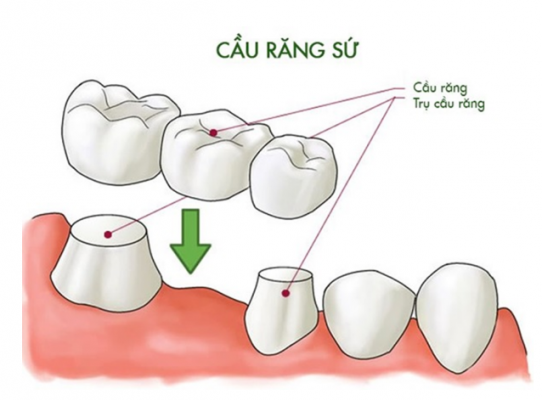

– Cầu răng sứ là một giải pháp khôi phục một hoặc nhiều răng mất cố định rất phổ biến hiện nay. Giống như bạn đi qua một chiếc cầu bắc qua sông cầu răng gồm 2 hoặc nhiều trụ cầu là các răng trên cung hàm hoặc các trụ implant và nhịp cầu là một hay nhiều răng bị mất. Các trụ cầu chính là các điểm tựa mang răng mất. Cầu răng được gắn cố định trên các răng trụ qua đó giúp lấp đầy khoảng trống răng mất trên cung hàm.

Hình ảnh cầu răng sứ